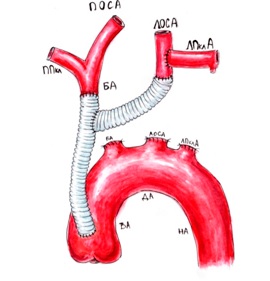

Нормальный диаметр корня аорты: медицинские нормы и отклонения